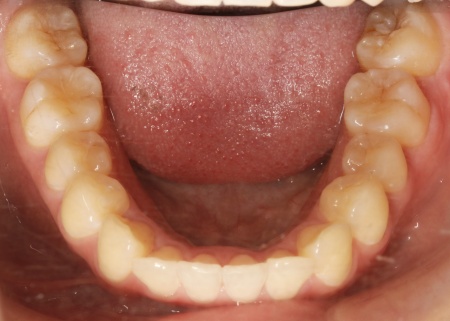

20代女性 乱れた上下の歯並びをハイブリッド矯正で改善した症例

拝見したところ、上下の歯はデコボコに生えている状態でした。

歯並びがある程度正しい位置に並んだら、マウスピース矯正で微調整を行いました。